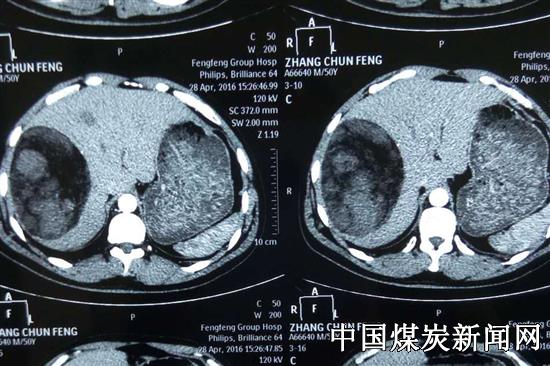

近日,一位50多岁患者就诊于邯郸市峰峰矿区冀中能源峰峰集团总医院外二科,他在近期的CT检查中发现右肝15×10厘米巨大肿瘤。总医院外二科年轻医师张浩、姜卫星在峰峰集团首席专家张海林的指导下,成功为其行解剖性右半肝切除术。

肝是人体的重要脏器,右半肝的大小在整个肝脏解剖中占比约百分之六十,该患者肝部巨大肿瘤紧贴大血管,术中容易发生难以控制的大出血,手术难度很大。累及第二肝门、第三肝门的肝部肿瘤手术的难点在于两处解剖的精细处理,传统的手术常规行第一肝门完全阻断,会使正常的左半肝供血产生不利影响,手术中的阻断时间要严格控制把握,如果手术时间过长,多需要二次阻断。此次手术为避免左半肝的供血不足产生肝功能损害,外二科医师们在手术中熟练进行了第一肝门、第二肝门的解剖行右半肝肝门阻断,解决了此项技术的两大难点,手术中不影响左肝的供血,可以从容进行右半肝及肿瘤切除。手术先处理第一肝门,结扎肝右动脉及门静脉右支,游离肝周韧带;然后解剖处理第三肝门,逐支结扎肝短静脉;最后解剖处理第二肝门,离断肝实质游离处理肝右静脉。为避免下腔静脉和肝组织撕裂导致的大出血,医师们小心翼翼缓慢游离出肝部各个重要管道进行结扎,对右半肝切除后仔细缝扎处理断面。